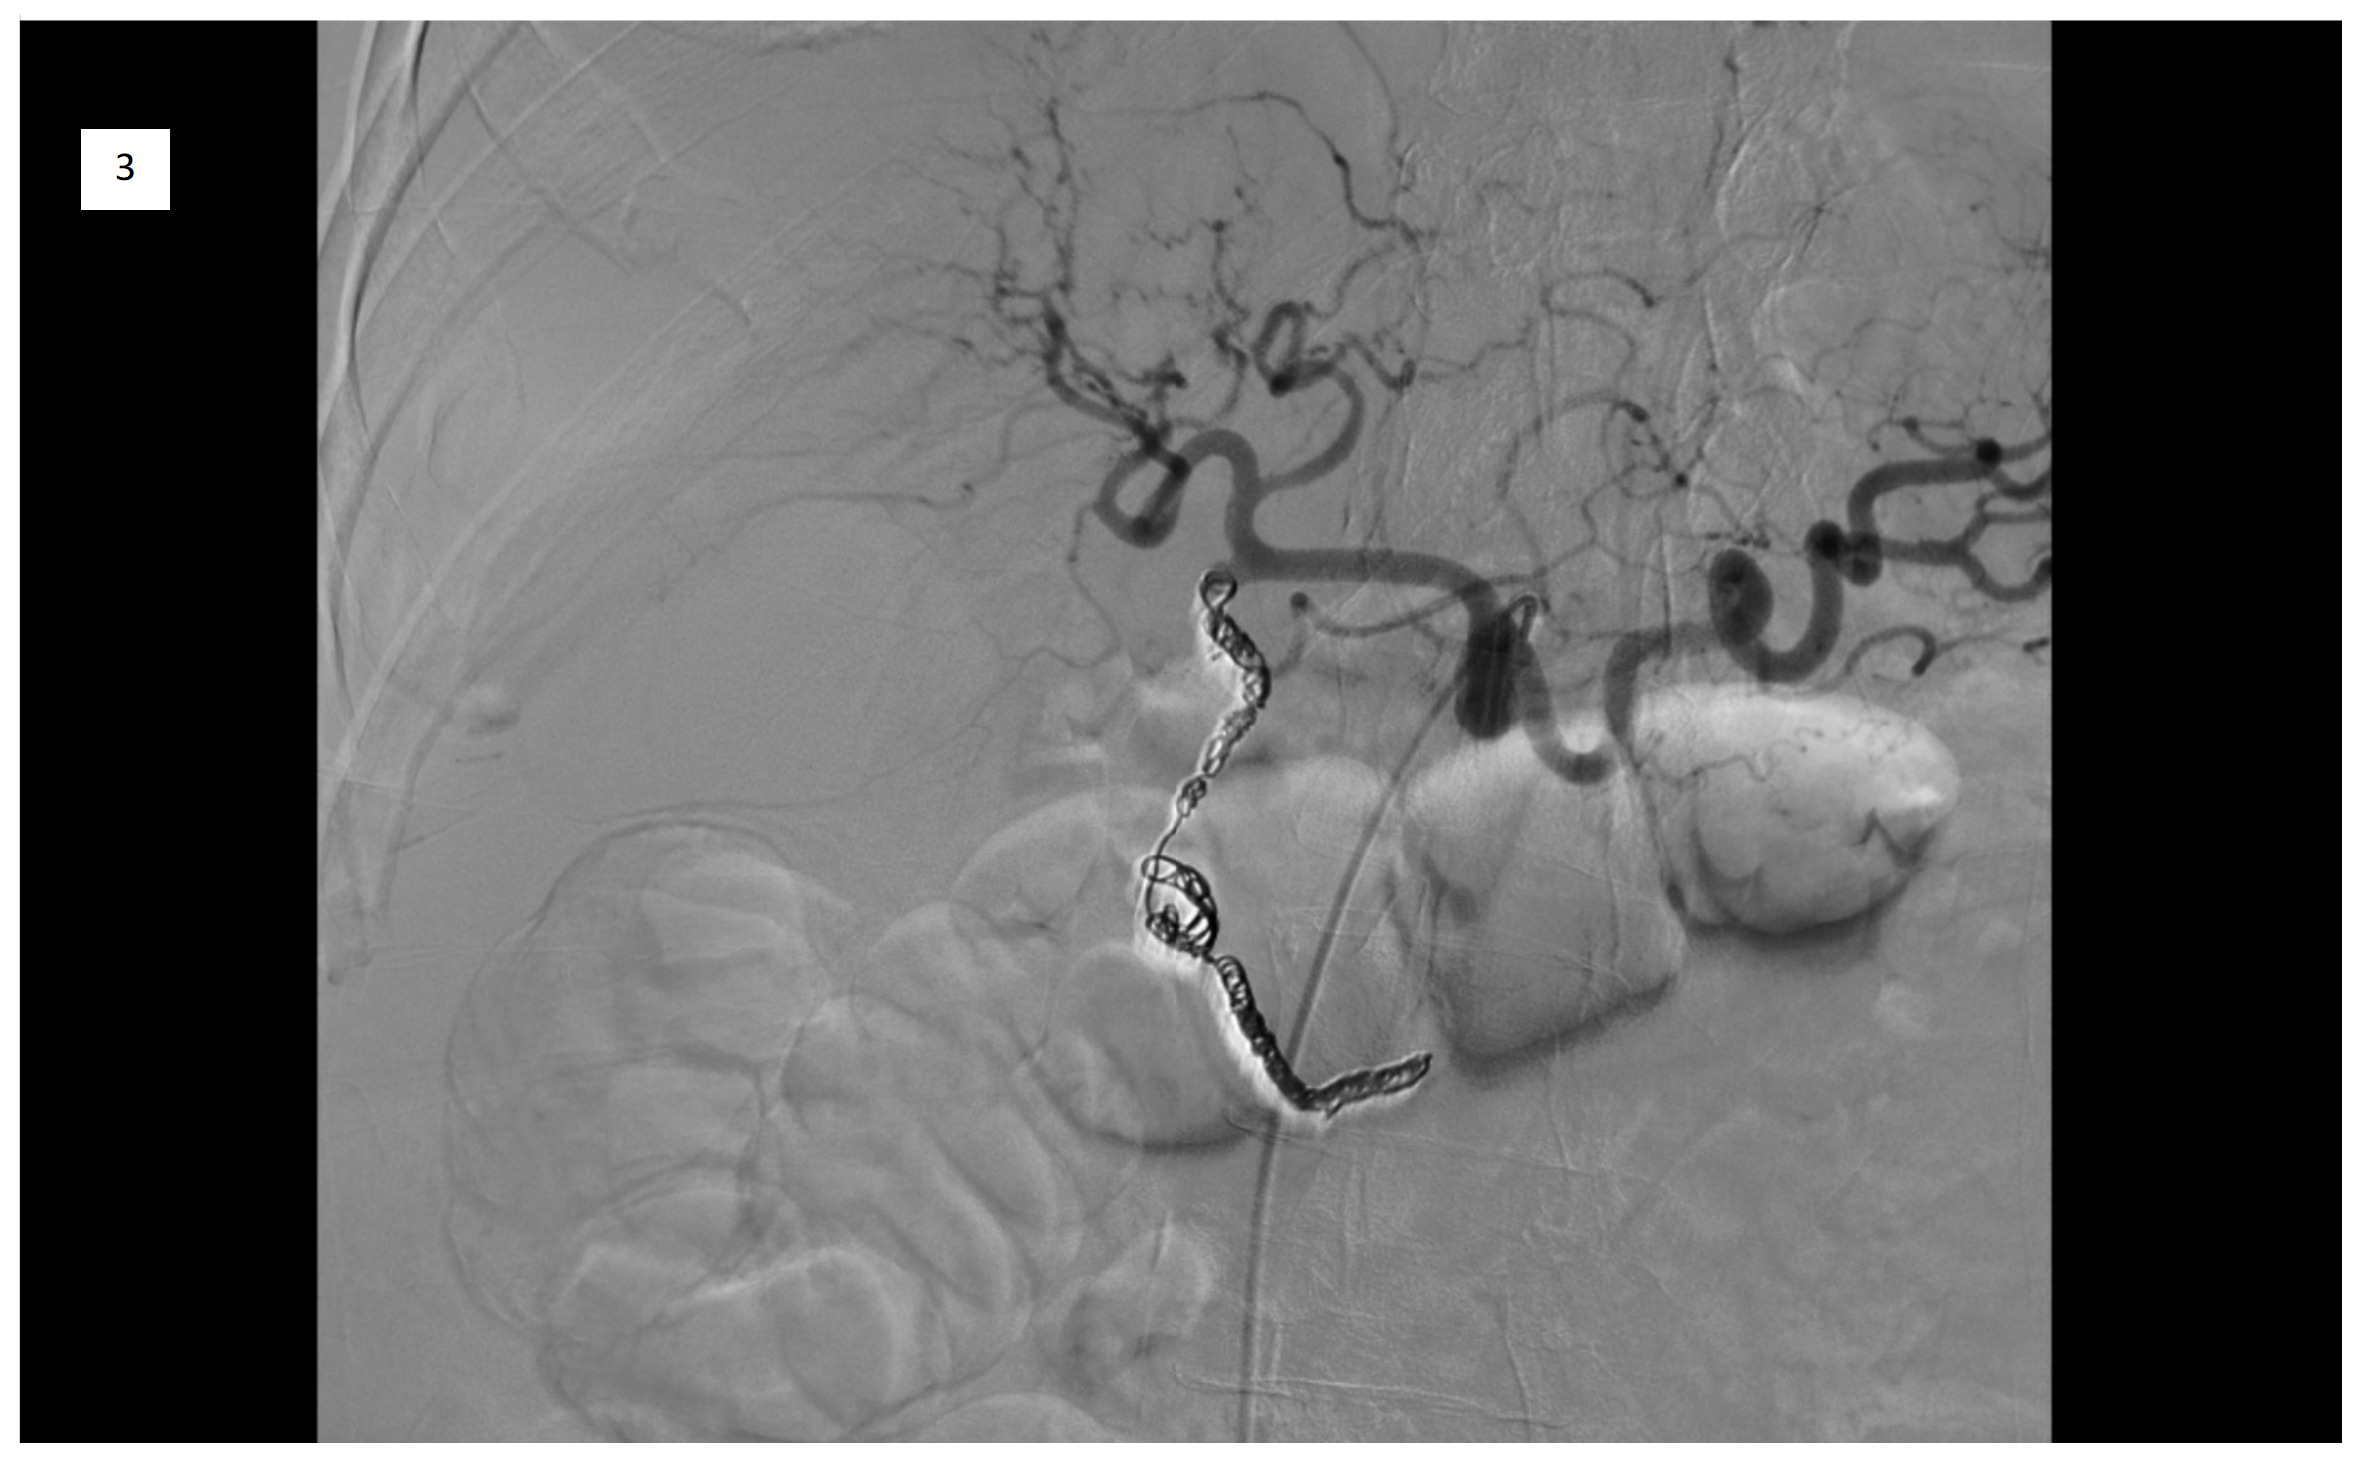

On day 2, an emergency Celiac artery angiography was performed by Interventional Radiology, which demonstrated a patent GDA with delayed and faint filling of a pseudoaneurysm centered in the GDA territory. The angiograms of the superior mesenteric artery (SMA) and the inferior pancreaticoduodenal artery (IPDA) demonstrated brisk filling of a large pseudoaneurysm in the GDA territory (Figure 2) and an additional, much smaller pseudoaneurysm more distally with a large feeding vessel from the IPDA. Subsequently, micro-catheterization of the SMA and retrograde catheterization of the proximal GDA were performed. Due to difficulties in deploying POD 6 and POD 4 coils, coil embolization was ultimately performed using multiple detachable and soft coils appropriately sized to the target vessels. Post-embolization angiography from IPDA demonstrated successful occlusion of the GDA and the large pseudoaneurysm, as well as that of large feeding vessels to the smaller pseudoaneurysm (Figure 3). A follow-up CT scan on day 3 confirmed resolution of the pseudoaneurysm and a stable hematoma.